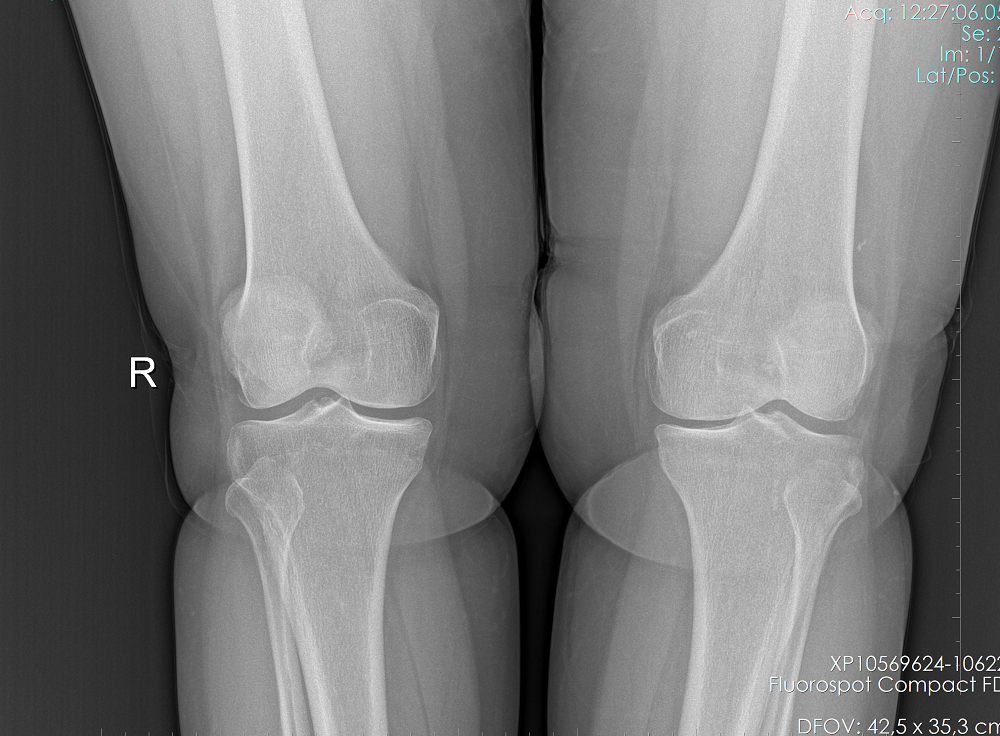

Gonartrozu olan hastanın ameliyat öncesi ve YTO yapıldıktan sonraki grafileri

Diz osteotomisi en çok 60 yaşın altındaki zayıf ve aktif hastalarda yapılır. Dizinin sadece bir tarafında ağrısı olan, çoğunlukla aktiviteden veya uzun süre ayakta durmaktan kaynaklanan diz ağrısı olan, dizini tam açan ve en az 90 derece bükebilen hastalar ameliyat için uygun adaylardır.

Diz osteotomisi, diz ekleminin sadece bir tarafına hasar görmüş olan erken evre osteoartritli hastalarda kullanılır. Bu işlem eklemin hasarlı tarafındaki yükün kaydırılmasıyla ağrıyı hafifletebilir ve artritli dizde işlevi önemli ölçüde iyileştirebilir.